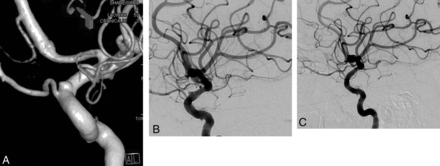

Preoperative 2D (A and B) angiograms show the ICA aneurysm in which the anterior choroidal artery is originating from the aneurysm at the neck. A single PED is placed covering the neck, causing stagnation of the contrast within the sac (C). Six-month control angiography (D) demonstrates total occlusion of the aneurysm with the anterior choroidal artery preserved (arrow).

Right internal carotid oblique angiogram (A) shows a right posterior communicating artery aneurysm (the ipsilateral P1 is aplastic and not shown) in a patient in whom previous endovascular attempts and clipping had failed, with surgical wrapping performed eventually. Two years after a single PED placement, the aneurysm is remodeled in the corresponding view (B).